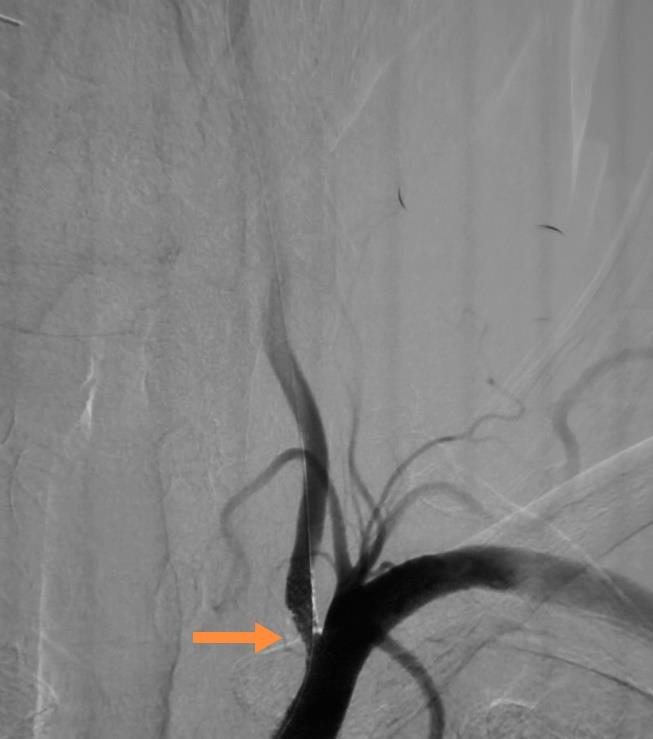

椎动脉重度狭窄支架植入术前术后DSA

冠脉动脉重度狭窄支架植入术前术后DSA

心内科介入团队为该患者先行冠脉造影提示左侧冠状动脉主干重度狭窄,先行支架植入术。然后,神经介入团队行全脑血管造影术,提示左侧椎动脉重度狭窄,遂行椎动脉支架植入术。术后患者胸闷、胸痛症状消失,头晕症状改善,目前已康复出院。